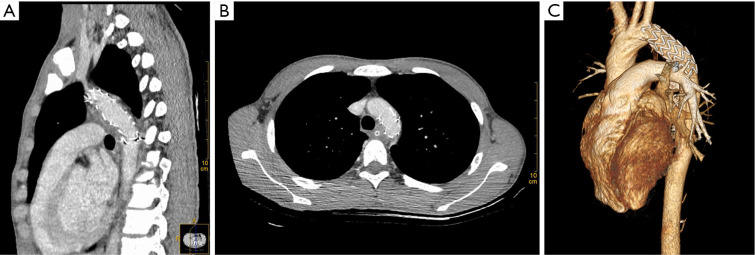

Case description: A 16-year-old male sustained severe multisystem organ injuries after a fall from a five-story building. The patient was critically ill and required intubation during transport. Emergency computed tomography (CT) revealed extensive injuries, including: a descending aorta injury with pseudoaneurysm, bilateral pulmonary contusions with moderate left hemothorax, right pneumothorax, retroperitoneal effusion, right renal contusion with perirenal hematoma, Fractures of the skull base, upper and lower jaw, lumbar spine, sacrum fractures, and severe open wounds in the mouth, right knee joint, and bilateral heels. A multidisciplinary team determined that aortic injury repair should be prioritized. We ultimately performed an unconventional endovascular aortic repair in this adolescent patient. The procedure was completed efficiently without complications, and subsequent interventions successfully addressed the remaining injuries. The patient required a total hospital stay of 733 days and underwent 13 surgical procedures before being successfully discharged following rehabilitation. As of September 2024, the patient remains alive with no complications related to the arterial injury.

Conclusions: TEVAR represents a safe and viable short-term treatment option for adolescents with multiple traumatic injuries. The 69-month follow-up in this case confirms procedural success and suggests the effectiveness of TEVAR in this patient population.